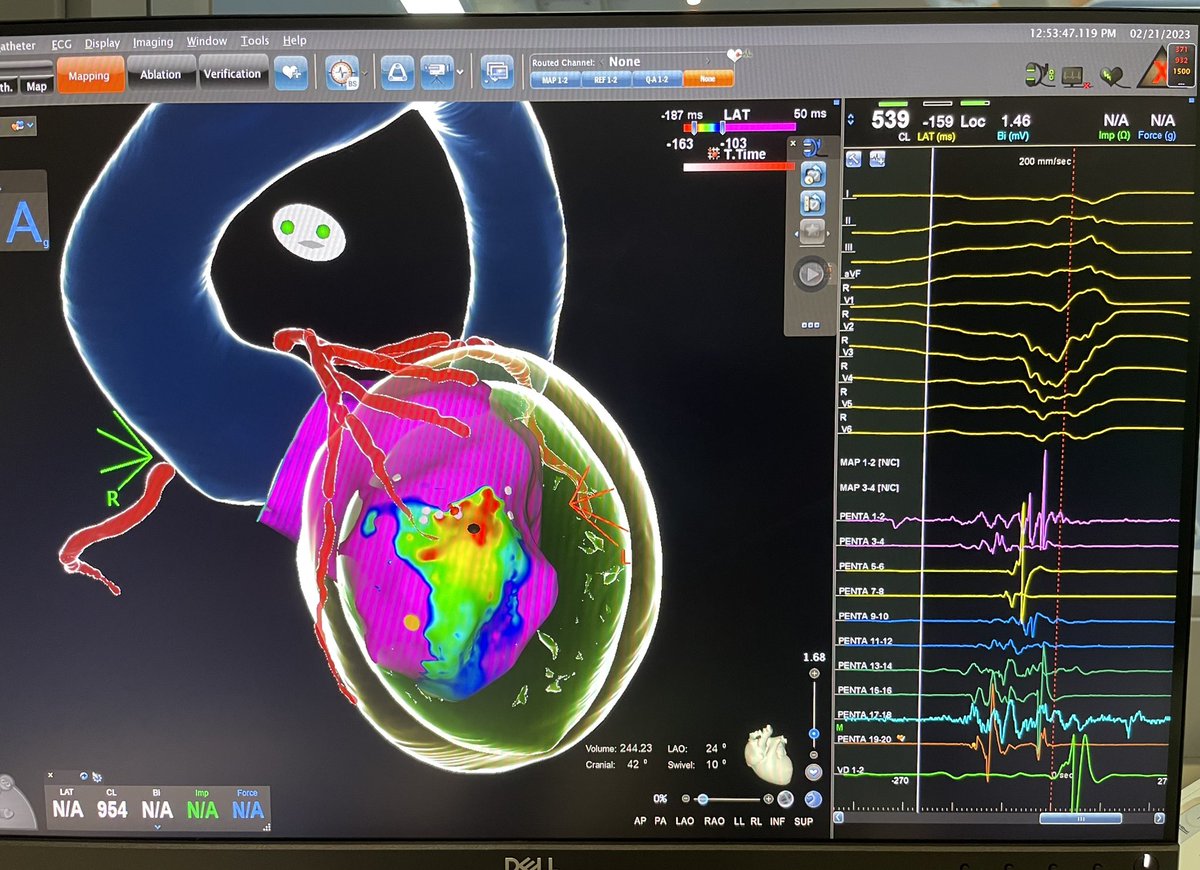

Incessant slow #VT with intramural circuit in end-stage HCM despite previous #VTablations. Coil insertion in a small branch of 2nd diagonal coronary artery. CT integration in the #EPlab❤️ at Miguel Servet University Hospital. #EPeeps @EPeeps_Bot @secardiologia @escardio